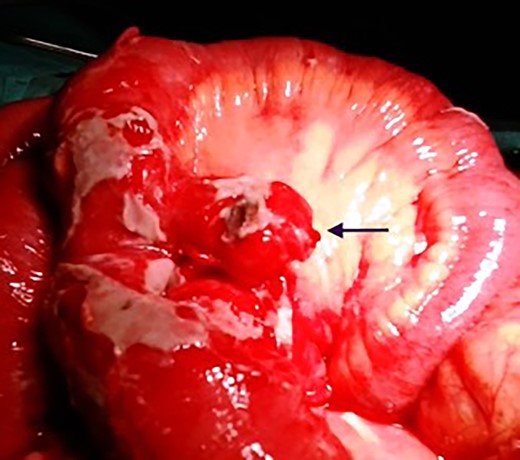

A 45-year-old patient admitted to the emergency unit was complaining of abdominal pain lasting for 3 days. Initially, the pain was located in the epigastric region, then secondarily generalized to the whole abdomen. He also reported vomiting related to food intake and bowel habit change. Physical examination revealed a good general condition, a temperature of 38.8 C°, a pulse rate of 120 heart beats/min, a blood pressure of 100/90 mmHg and a respiratory frequency of 28 cycles/min. There was an abdominal distension with a widespread tenderness. Plain abdominal radiography showed air-fluid levels and was suggestive of abdominal effusion (Fig. 1). On biology, blood cell count was 12 400 cells/mm3 (normal range: 4000–10 000) and creatinine was 16.8 mg/l (normal range: 6–12). A generalized peritonitis was then suspected, and a laparotomy was performed. On exploration, we found 400 ml of seropurulent peritoneal fluid and a perforated Meckel's diverticulum of 3.5 cm in size, which was located 60 cm from the ileocecal junction on the mesenteric edge of the ileum (Fig. 2). The patient underwent a removal of the diverticulum by a segmental resection of the ileum with an end-to-end anastomosis. The postoperative course was marked by persistent peritonitis, which motivated a revision surgery that involved a peritoneal lavage and drainage. Second, the postoperative course was uneventful. Pathological examination of the surgical specimen found a perforated diverticulitis without heterotopic tissue.

Intraoperative findings of perforated mesenteric Meckel diverticulum.